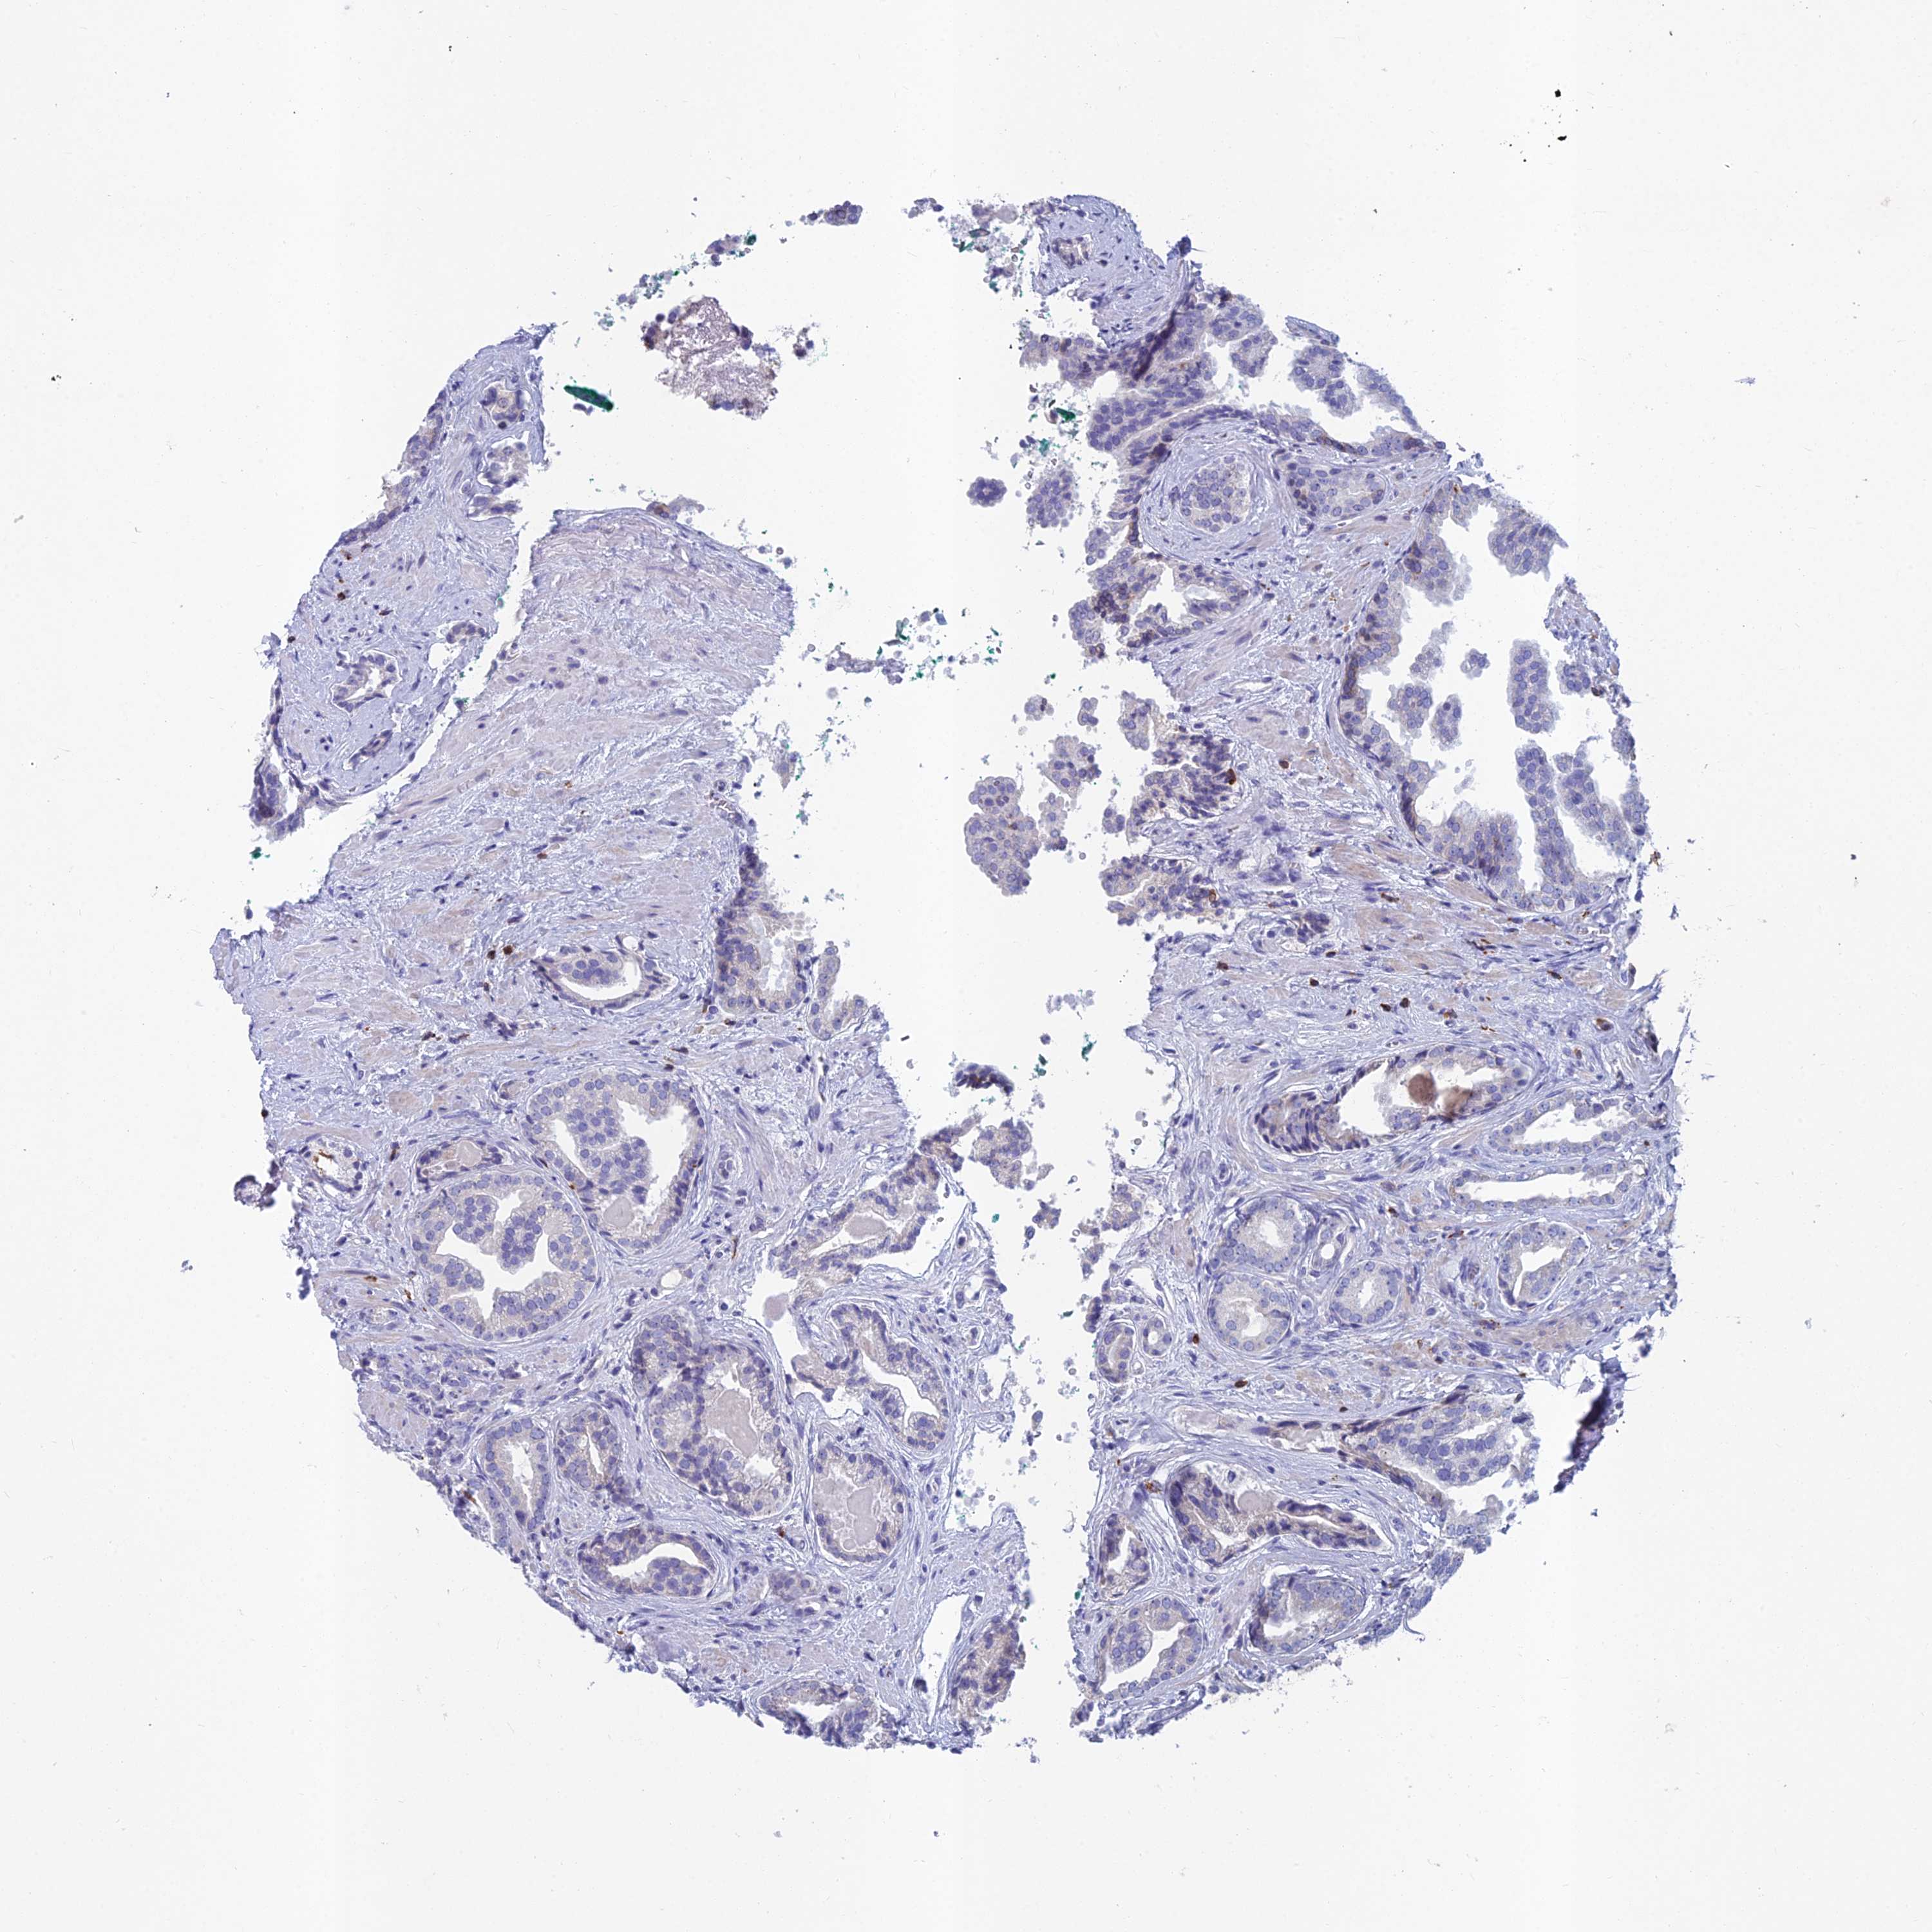

PROSTATE CANCER - Protein expressioni

A mouse-over function shows sample information and annotation data. Click on an image to view it in a full screen mode. Samples can be filtered based on level of antibody staining by selecting one or several of the following categories: high, medium, low and not detected. The assay and annotation is described here.

Note that samples used for immunohistochemistry by the Human Protein Atlas do not correspond to samples in the TCGA dataset.

Antibody stainingi

Antibody staining in the annotated cell types in the current human tissue is reported as not detected, low, medium, or high, based on conventional immunohistochemistry profiling in selected tissues. This score is based on the combination of the staining intensity and fraction of stained cells.

Each image is clickable and will lead to virtual microscopy that enables deeper exploration of all samples and also displays staining intensity scores, fraction scores and subcellular localization as well as patient and tissue information for each sample.

Antibody HPA044127

Staining

High

Medium

Low

Not detected

Intensity

Strong

Moderate

Weak

Negative

Quantity

>75%

75%-25%

<25%

None

Location

Nuclear

Cytoplasmic/membranous

Cytoplasmic/membranous,nuclear

Adenocarcinoma, High grade

Adenocarcinoma, Low grade